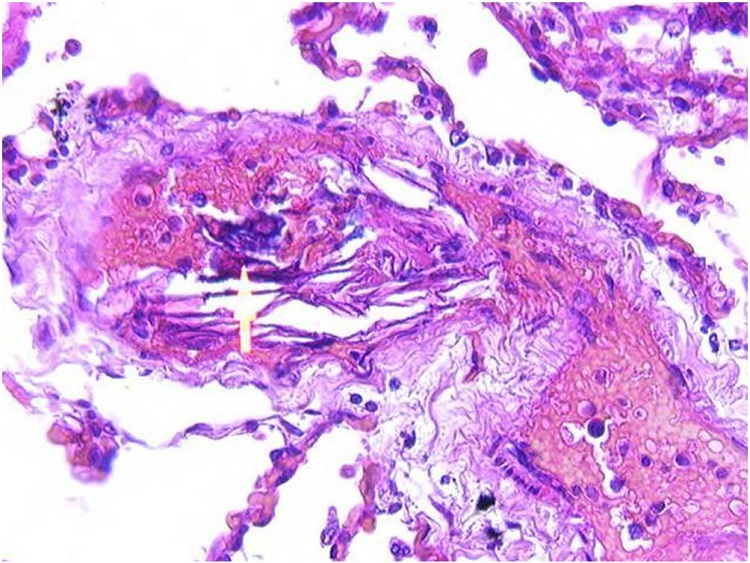

Autopsy revealed numerous small pulmonary blood vessels containing squamous cells (Figure 1), many surrounded by cleared space in the luminal blood, and some accompanied by small calcifications (Figure 2). The squamous cells were positive on immunohistochemical stain for cytokeratin AE3 (Figure 3). Mucinous material was identified in scattered small pulmonary blood vessels on mucicarmine stain. Autopsy revealed many sites of hemorrhage in heart, stomach, duodenum, kidneys, bladder, vagina and pelvis, and 1000 mL of partially clotted blood in the abdominal cavity. The pleural cavities contained serous fluid, 210 mL on the left and 550 mL on the right. There was pulmonary congestion and edema, with a combined lung weight of 1080 grams. There were occasional fibrin thrombi in renal glomeruli.

Examination of the placenta showed an intact complete 496-gram placenta with no significant abnormalities. Examination of the uterus from the hysterectomy showed decidualized endometrium and cervical foci of hemorrhage with blood vessels containing anucleate squames.